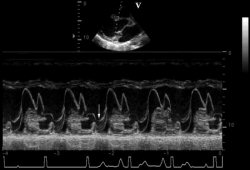

Posterior mitral valve prolapse on M-mode echo

From the collection of Samir Kapadia and Mehdi H. Shishehbor

See this image in context in the following section/s: